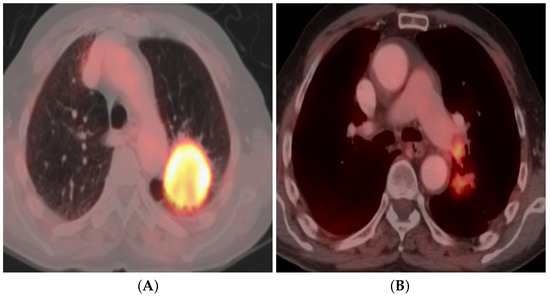

3.4. Positron Emission Tomography (PET/CT)

3.4.3. Qualitative Image Analysis

3.4.4. Quantitative Image Analysis

3.4.6. Dual-Time-Point FDG PET/CT